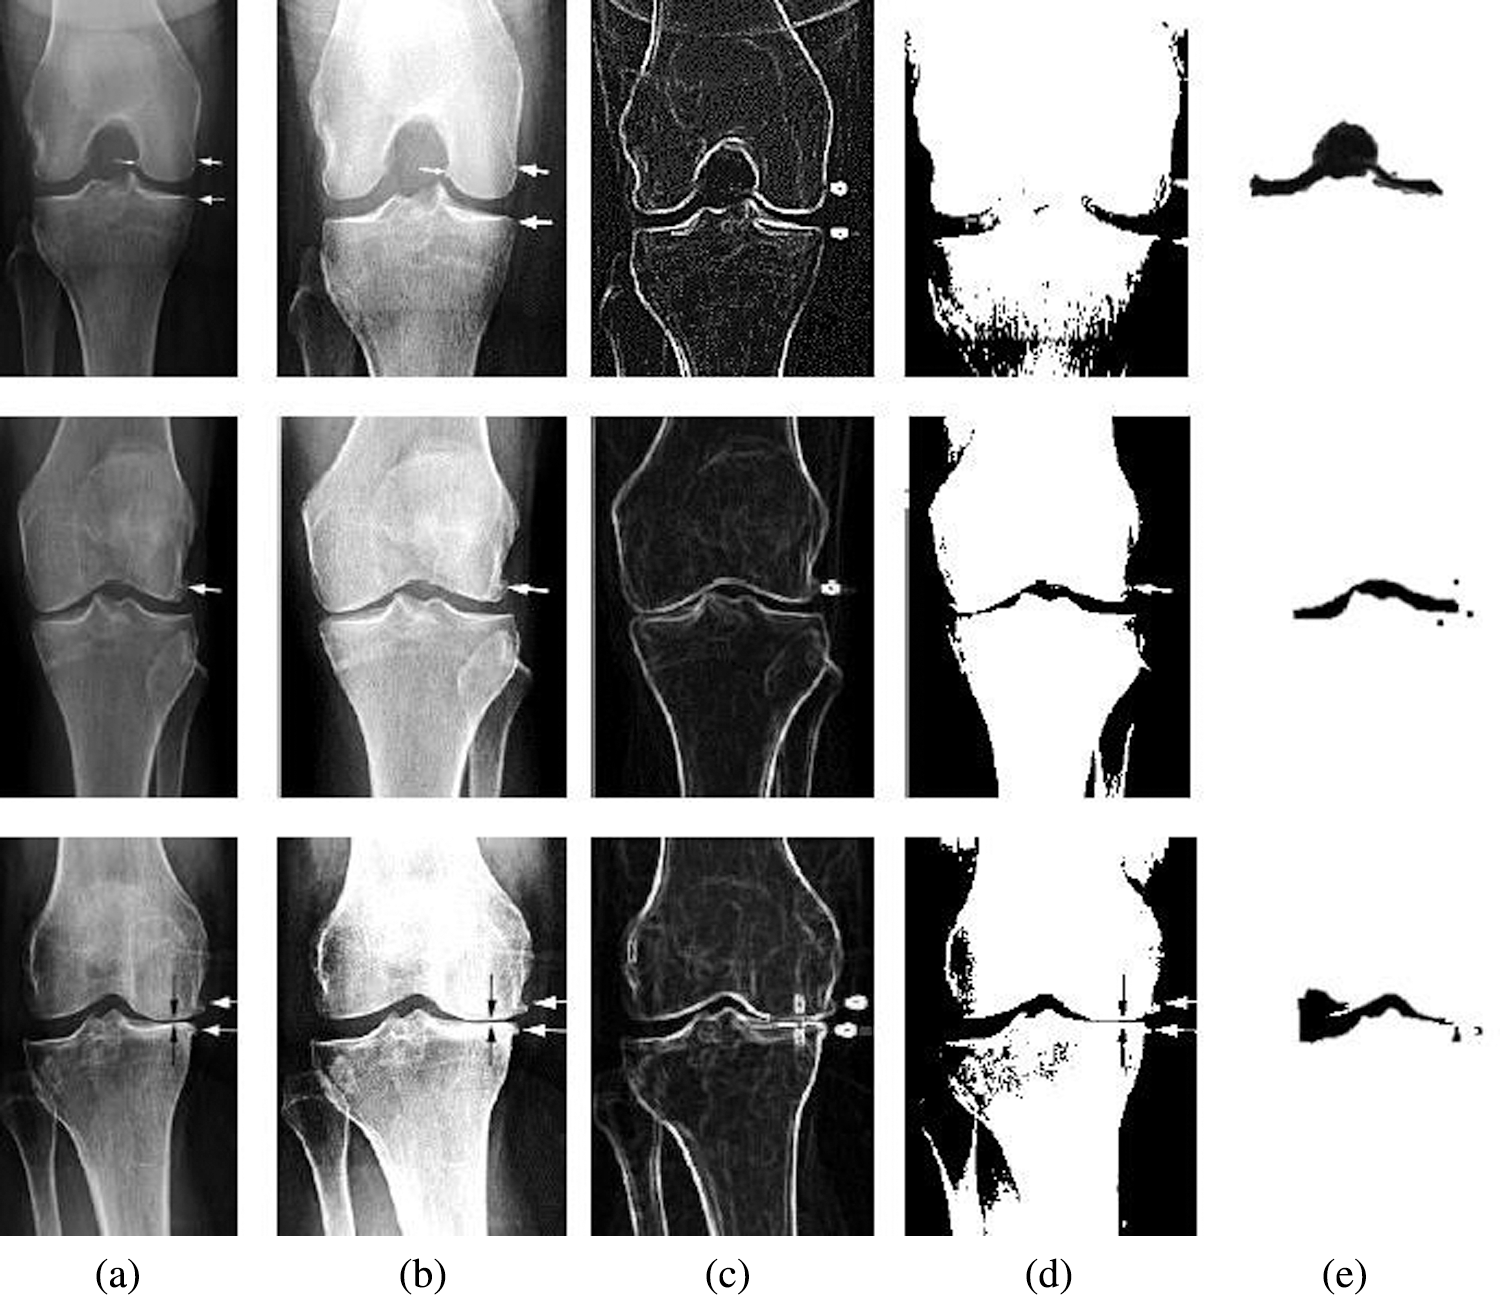

The experimental result of Knee OA CT image using a correlation histogram analysis and the optimized thresholding is analysed through different steps;

From the experimental analysis, it is obvious that the osteoarthritis can be analysed and processed by this technique. As we mentioned in Fig. 6b the input CT image is enhanced using correlation histogram analysis that increased the intensity of the image. In Fig. 6c thresholding concept is applied that segmented the enhanced CT image based on Niblack and Bernsen algorithm as shown in Fig. 6d. Finally the segmented image is optimized using Elephant Herding optimization that isolated the osteoarthritis. Experimental result of the proposed technique is compared with different existing techniques to evaluate its performance.

Figure 6: Experimental result of the proposed method with CT image samples (a) Sample images (b) Contrast enhanced image using correlation histogram (c) Thresholding (d) Niblack and Bernsen output (e) EH Optimized image